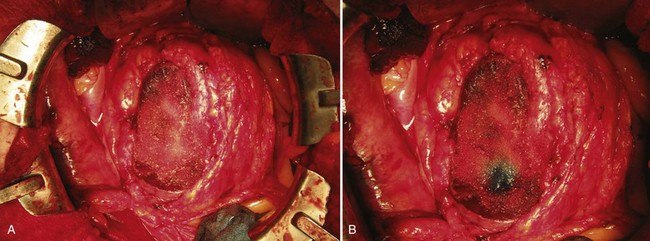

An anterior cavotomy is made using Potts forward and reverse scissors. The cavotomy should circumscribe the ostium of the renal vein and extend to the minor hepatic veins above the caudate lobe of the liver. The field will be nearly bloodless. For tumor extending into the right atrium the atrium is also opened (Fig. 54–115). The thrombus is extracted with the patient in Trendelenburg position and using positive-pressure respiration. If possible, the tumor thrombus is removed intact along with the kidney, although the thrombus may need to be removed in pieces if it is friable or adherent to the caval wall (Fig. 54–116). When necessary, a Fogarty catheter is passed from the atrium into the hepatic veins to retrieve portions of tumor thrombus. The authors ensure that tumor thrombus removal is complete by performing venacavoscopy with a flexible cystoscope. The cavotomy is closed with a double-armed 4-0 polypropylene running suture. The atriotomy is closed. Radical nephrectomy is carried out while rewarming to 37° C and coming off bypass. The patient is decannulated. Protamine is administered to reverse the heparin. Any leaking areas on the IVC are repaired with interrupted 4-0 polypropylene sutures. The abdomen is drained, and chest tubes are placed. Fresh frozen plasma, platelets, and desmopressin are used if needed to treat coagulopathy.

Figure 54–115 A and B, Tumor thrombus extension into right atrium removed using traditional median sternotomy approach and an atriotomy for retrieval of thrombus. IVC, inferior vena cava.

(A, © The Lahey Clinic. B, From Wotkowicz C, Libertino JA, Sorcini A, Mourtzinos A. Management of renal cell carcinoma with vena cava and atrial thrombus: minimal access vs. median sternotomy with circulatory arrest. BJU Int 2006;98:289–97.)